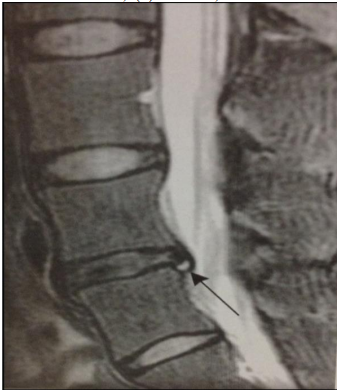

Na imagem a seguir, apresentada no manuscrito de Vieira, Predes e Pereira. Rev JRD de Estudos Acadêmicos. 2021;4(8):4667046, a seta indica:

Enunciado 3203126-1